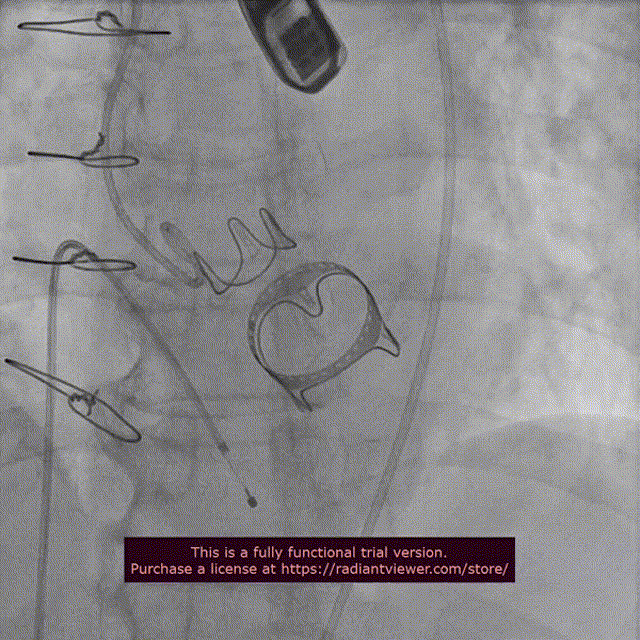

近日,中国医学科学院阜外医院潘湘斌教授团队,在多科室的通力配合下,凭借扎实的手术功底顺利完成一例经导管主动脉瓣和二尖瓣瓣中瓣置换术。

手术过程